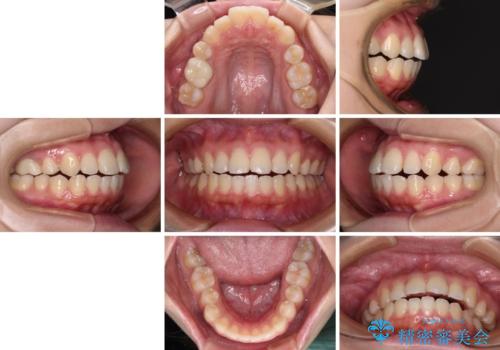

再矯正 開咬に後戻りした歯列をインビザラインで改善

- 矯正治療の後戻りを気にして来院された患者様です。

デコボコと上下前歯の隙間が気になるものの、しっかりと治療をしたいという意思はないとのことで、インビザラインの中でもアライナー数に制約のあるライトパッケージを用いて、治療できる範囲まで歯列を改善していくこととしました。

インビザラインは前歯部の開咬に効果的であることが多く、ライトパッケージにもかかわらず、十分満足のいく仕上がりとなりました。